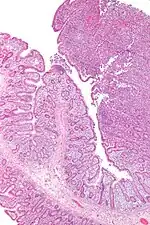

Linfoma de células T associado a enteropatia (EATL) é um tipo de linfoma das células T que afeta o intestino delgado. É o tipo mais comum de linfoma das células T gastrointestinais, partindo dos linfócitos T entre as células que revestem o intestino delgado.[1]